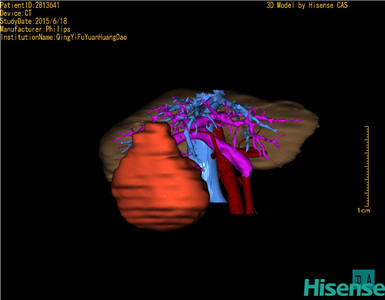

CT结果输入海信CAS系统后行3D重建及手术规划后,于2015-6-29全麻下行“右半肝切除+胆囊切除术”手术治疗:

术前三维重建及手术方案设计:

将0.625mm双源薄层CT资料的静脉期和动脉期Dicom格式文件导入海信CAS系统。

通过调节窗宽窗位调整CT序号,对肿瘤,肝实质,胆囊,下腔静脉,肿瘤,肝动脉、门静脉及肝静脉等进行三维重建;系统自动计算肿瘤体积和肝脏体积。

模拟手术操作,自动计算切除肿瘤体积。肝脏体积为1058ml,肿瘤体积为562.1ml,肿瘤体积为肝脏体积的53.1%,通过比对60-70岁正常肝脏体积为1262.7±284.31 ml,通过术前模拟手术,精准判断切除后剩余肝脏体积能耐受,避免肝衰竭发生。

术前手术方案的规划。

术前三维重建:

重建图片